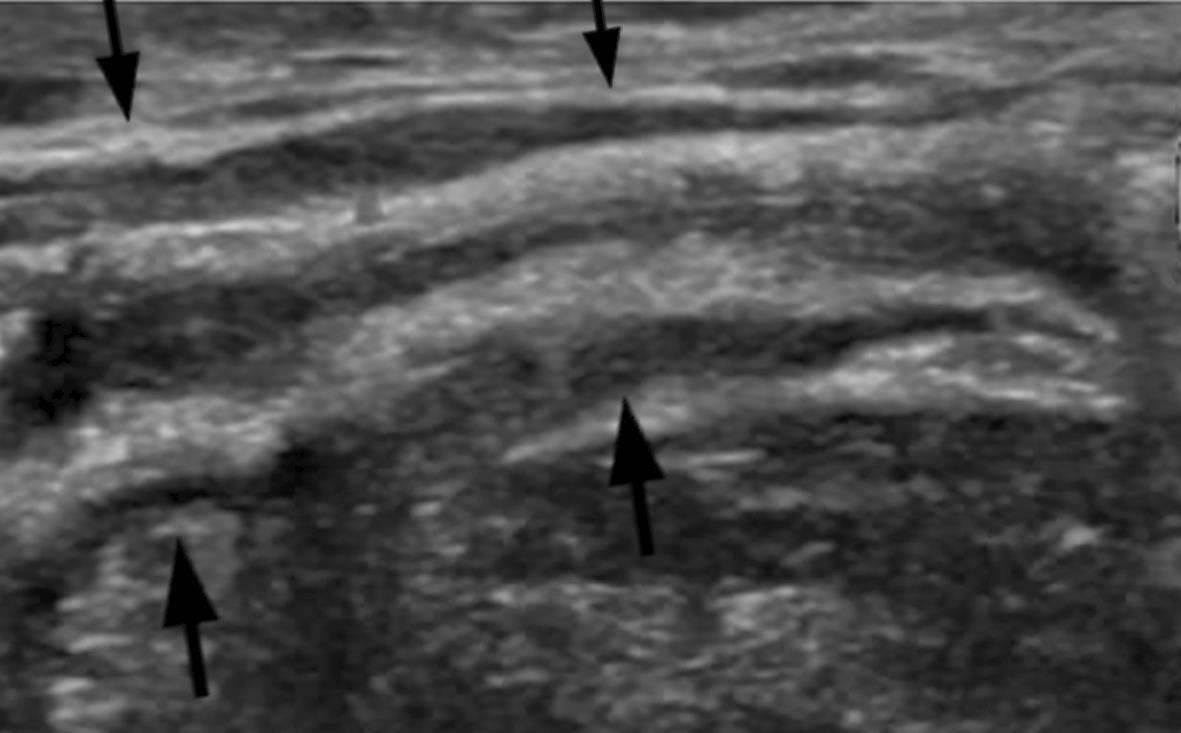

Hollow viscera abnormalities

Gallbladder wall thickening

Bowel wall thickening

Bowel dilation

Gastric distention

Urinary bladder thickening

Peritoneal abnormalities

Small ascites

Mesenteric abnormalities

Mesenteric lymphadenopathy

• Gastrointestinal (GI) symptoms (abdominal pain, diarrhoea and vomiting) are prevalent in MIS-C

• Abdominal pain in 62%

• Up to 90% any GI symptom

• Anumber of studies have described abdominal imaging findings including ascites, bowel wall thickening and mesenteric lymphadenopathy